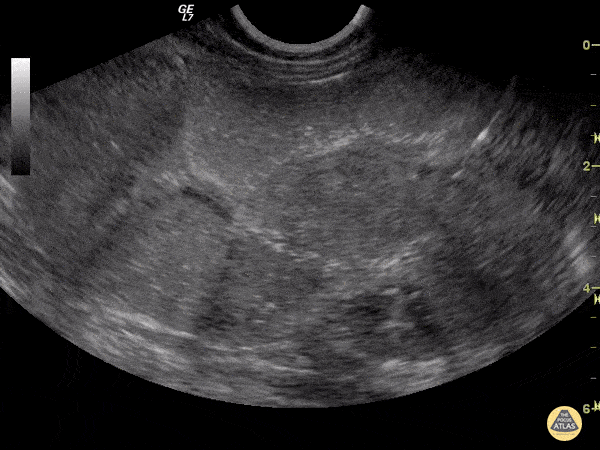

Here we can see an intussusception. Multiple layers and concentric rings, target configuration on cross-sectional imaging. Evgeny Domanin